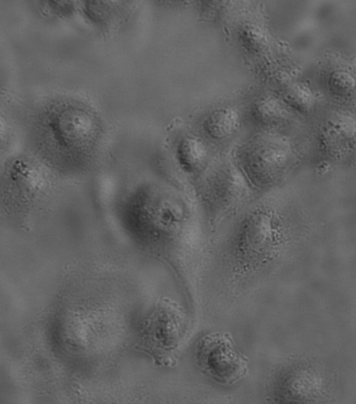

MCF-7细胞怎么是这个样子呢?

大家好,最近在养MCF-7细胞,刚拍完照片,发现细胞状态好像不对!

求鉴定?细胞是不是死了啊?

10倍

lz倒置显微镜的滤光片与物镜没匹配使用,10倍与20倍拍的有差别,MCF-7细胞内细胞器是否有增多?培养液是否变浑浊?细胞生长快还是缓慢?LZ试试用40倍配合PH2的滤光片观察细胞,可以做个支原体检测

细胞要是漂的或半悬浮就是死了。这上面看不出来。从图上看细胞状态不好,正常应该成呈梭形或长条状,细胞排列规整,细胞间隙明显,视野干净,透亮。图中细胞器肿胀,应该活不了太久。